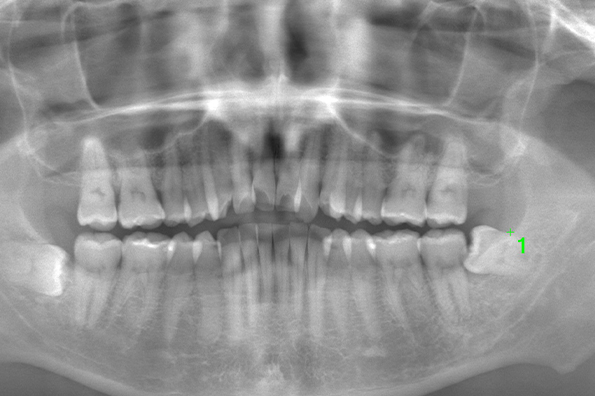

CASE 1

基本情報

| 年齢・性別 | 30代・女性 |

| 主訴 | 左右に分けて親知らずを抜きたい、できれば痛くなく抜きたい |

| 親知らずのはえ方 | 完全に出ていてまっすぐはえている |

| 抜歯期間 | 15分 |

| 抜歯費用 | 約2,000円(保険内) |

| 抜歯内容 |

何度か虫歯になり痛みはないが早めに抜きたい。 完全に頭が出ているため歯ぐきを切ったり骨を削らずに抜歯しました。 根の形も単純なため抜歯自体は5分もかからず上下ともに終わりました。 術後痛みや腫れも出ていません。 抜歯後は感染をしやすいため必ず抗生物質を飲み切ってください。 |